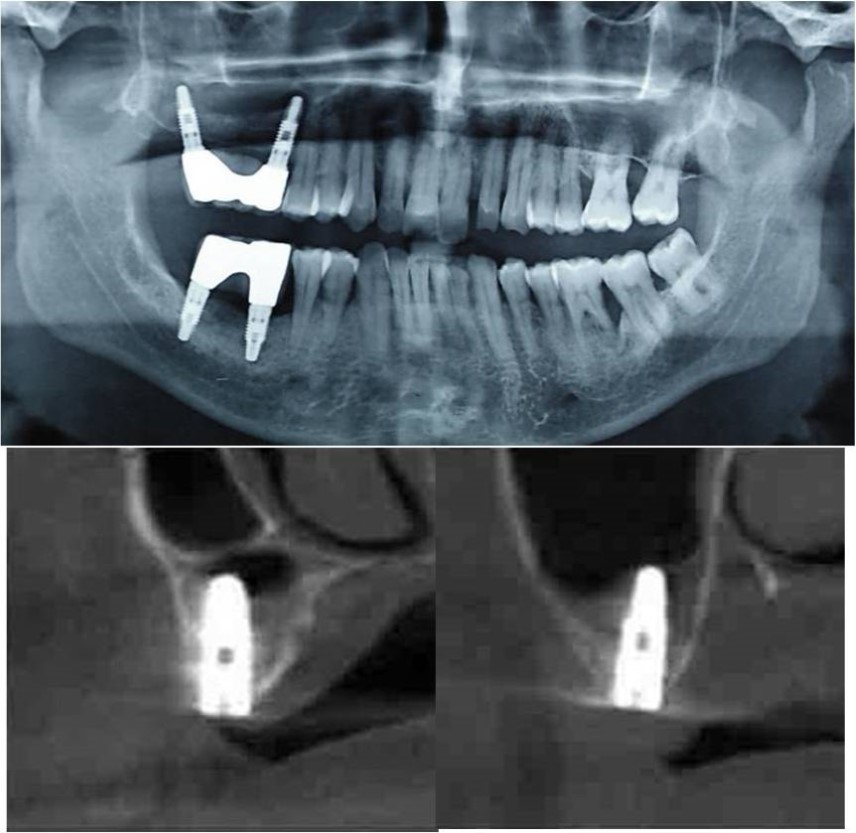

Figure 9.(a,b) Pre-treatment OPG and cross section of CBCT showing residual alveolar bone height for Case No.2

Figure 10.(a,b) Post-treatment OPG and cross section of CBCT showing residual alveolar bone height for Case No.2

Clinical and Radiological Assessment:

1.Partially edentulous maxillary and mandibular arches with missing 17, 26, 45, 46;

2.Increased pneumatisation of right maxillary sinus;

3.Height of available bone- 6.6mm;

4.Transverse thickness of available bone (CBCT evaluation)- 11mm;

5.Inter-ridge space adequate to place implant (10mm).

Treatment:

Patient underwent the procedure of indirect sinus elevation using sinus osteotomes in relation to 17 region. Calcium phosphosilicate putty was dispensed as the graft material through the crestal osteotomy site to maintain the elevated sinus membrane followed by placement of a dental implant measuring 5 x 10mm under local anaesthesia and strict aseptic protocols .The implant was allowed to osseo-integrate for a period of six months during which the patient was followed-up periodically and was assessed for peri-implantitis, crestal bone loss and mobility. At the end of 6 months, a repeat CBCT scan was advised to evaluate the increase in bone height. (Figure 9a,b, pre-treatment; Figure 10a,b, post-treatment)